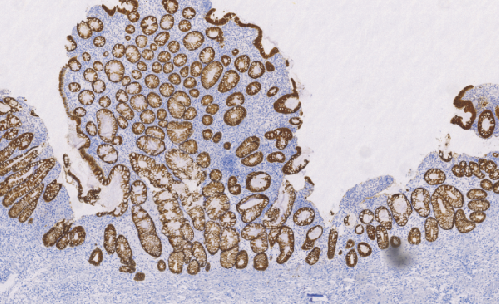

Mucin-4 Glycoprotein鼠抗人粘液素糖蛋白4单克隆抗体

几乎所有的粘膜表面都有粘蛋白跨膜蛋白保护。MUC-4在保护和润滑中起到重要作用的。表达于胸腺、甲状腺、肺、气管、食管、胃、小肠、结肠、前列腺、卵巢、子宫、胎盘、乳腺和唾液腺。在某些上皮细胞所产生的肿瘤中表达,如肺癌,上消化道的鳞状细胞癌,乳腺癌,胆道,结肠,宫颈癌。最小或不表达于正常胰腺或慢性胰腺炎,但在胰腺肿瘤和胰腺癌细胞株中高表达。

- 阳性部位:胞质

- 适用组织:石蜡切片

- 预处理:热修复